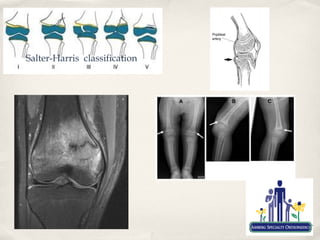

Salter-Harris classification

Fractures

✤   Distal Femoral and Proximal Tibial Physeal fractures

✤   Most common fractures mistaken for ligament injury

✤   Need a high index of suspicion

✤   Treat as such until proven otherwise

✤   Can be most devastating to growth and life/limb

✤   Non-displaced fractures can usually be treated in a cast

✤   Displaced or intrarticular fractures frequently require

surgery